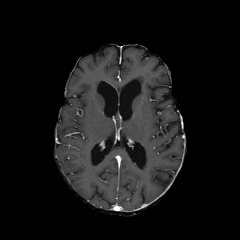

Objectives: This work aims to explore the impact of multicenter data heterogeneity on deep learning brain metastases (BM) autosegmentation performance, and assess the efficacy of an incremental transfer learning technique, namely learning without forgetting (LWF), to improve model generalizability without sharing raw data. Materials and methods: A total of six BM datasets from University Hospital Erlangen (UKER), University Hospital Zurich (USZ), Stanford, UCSF, NYU and BraTS Challenge 2023 on BM segmentation were used for this evaluation. First, the multicenter performance of a convolutional neural network (DeepMedic) for BM autosegmentation was established for exclusive single-center training and for training on pooled data, respectively. Subsequently bilateral collaboration was evaluated, where a UKER pretrained model is shared to another center for further training using transfer learning (TL) either with or without LWF. Results: For single-center training, average F1 scores of BM detection range from 0.625 (NYU) to 0.876 (UKER) on respective single-center test data. Mixed multicenter training notably improves F1 scores at Stanford and NYU, with negligible improvement at other centers. When the UKER pretrained model is applied to USZ, LWF achieves a higher average F1 score (0.839) than naive TL (0.570) and single-center training (0.688) on combined UKER and USZ test data. Naive TL improves sensitivity and contouring accuracy, but compromises precision. Conversely, LWF demonstrates commendable sensitivity, precision and contouring accuracy. When applied to Stanford, similar performance was observed. Conclusion: Data heterogeneity results in varying performance in BM autosegmentation, posing challenges to model generalizability. LWF is a promising approach to peer-to-peer privacy-preserving model training.